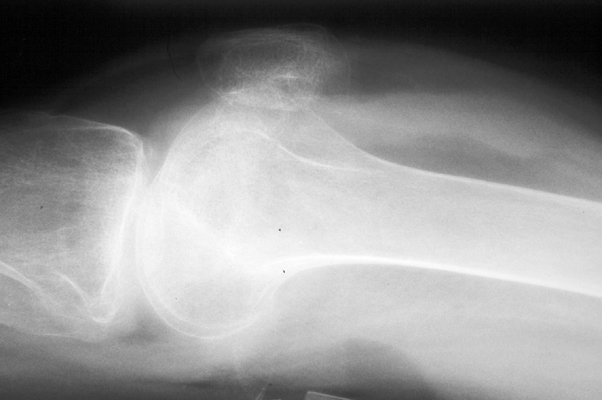

Fat fluid interface seen on the multiple lateral radiographs of the knee secondary to lipohemarthrosis. The fat-blood interface (FBI) is a very suggestive sign of underlying fracture extending into the joint. If no fracture is readily identified, diligent search should be undertaken.

Cross table lateral knee - Click on the image for a larger versionACross table lateral - Click on the image for a larger versionB